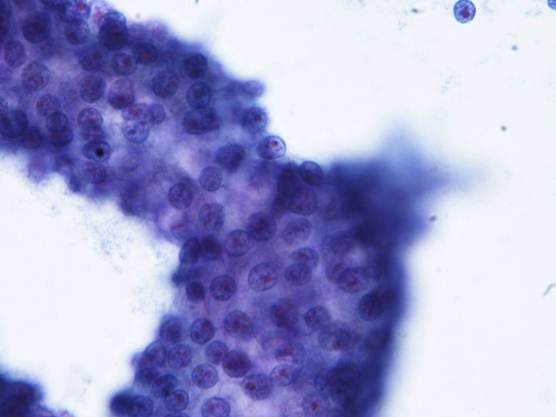

細胞質は境界不明瞭で、ライトグリーンに淡染する顆粒が認められた。

核は一部裸核状になり、小型類円形を呈し、クロマチンは細顆粒状で増量していた。

核小体は1個で赤く軽度腫大していた。